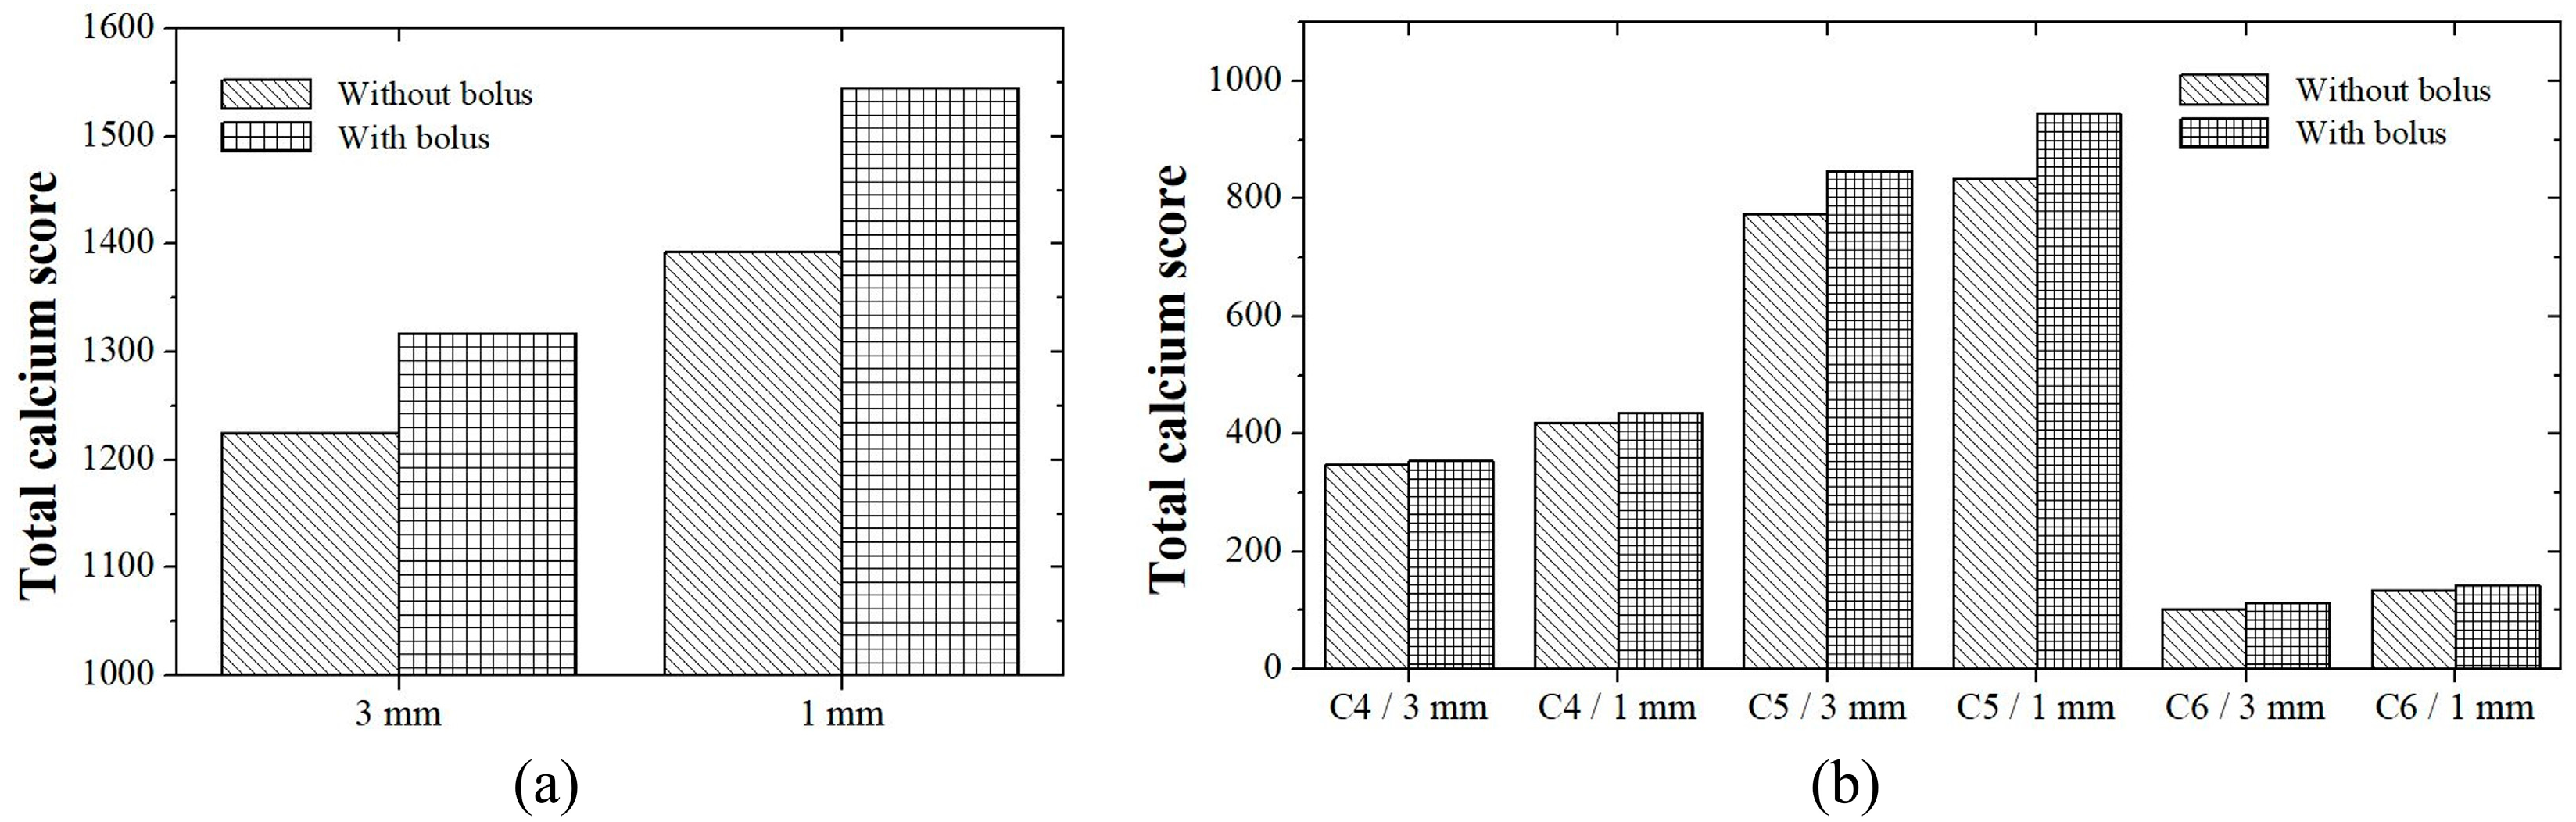

3. Results

3.1. Patient Study

3.2. Phantom Study